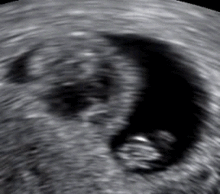

| An ultrasound showing an empty sac, a gestational sac containing a yolk sac but no embryo. This is a type of miscarriage. | |

An anembryonic pregnancy (also called an "empty sac" or "blighted ovum") is a condition where the gestational sac develops normally, while the embryonic part of the pregnancy is either absent or stops growing very early. This accounts for approximately half of miscarriages. All other miscarriages are classified as embryonic miscarriages, meaning that there is an embryo present in the gestational sac. Half of embryonic miscarriages have aneuploidy (an abnormal number of chromosomes).[20]